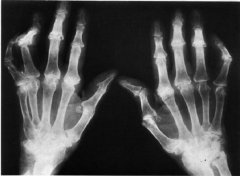

• “汤圆”还能治类风湿,奇了个怪!6月27日 听马友文主任讲解

• 类风湿久治不愈反反复复 经我院科学治疗康复

家住成都市郫都区的任阿姨,患有类风湿性关节炎12年多,一直口服 ...

• 钻井工人长期露天作业患上类风湿性关节炎

宋先生是一名钻井工人,长期的在潮湿的井下工作使他患上了类风湿 ...